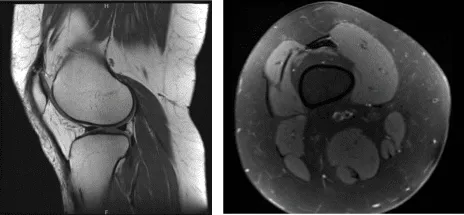

The patient’s MRI results showed minimal chondral wear over the patella and lateral tibial plateau. No evidence of meniscal tears. Mild patellar tendinosis.

Right Knee X-ray

MRI Right Knee Non-contrast